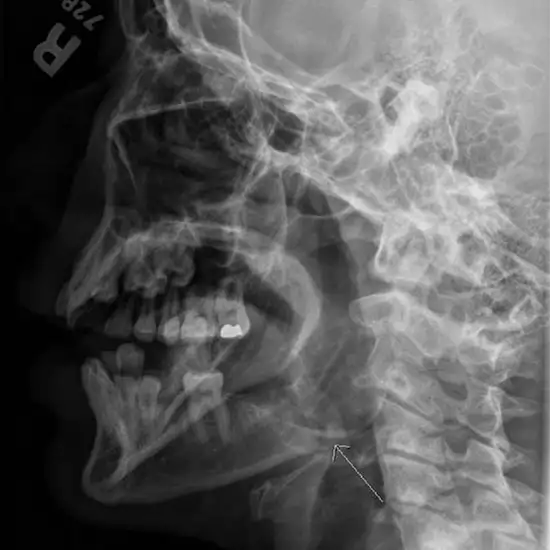

X-ray Mandible Left Lateral Oblique Test is used to examine the mandible structure, the temporomandibular joint (TM joint), and the surrounding muscles and soft tissues.

• Any jaw pain, discomfort, or difficulty moving may be diagnosed by doing a jaw movement test.

• For any impacted teeth to be found (wisdom teeth)

• To determine whether there are any jaw fractures or dislocations.

• To determine whether there is an infection, inflammation, cyst, or tumor in the jaw.